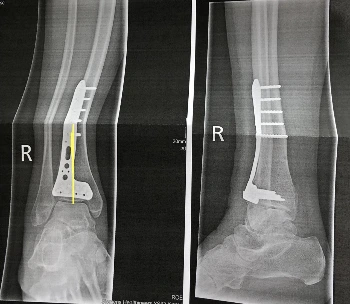

얼마 뒤 직원이 종이봉투를 가져다줬다. 열어봤더니 엑스레이 사진이 있었는데 아니... 뭐 이렇게 큰 철판이랑 나사를 이렇게 많이 박아놨나 충격적이었다. 일 년 뒤에 다시 열어서 철판이랑 나사 꺼내야 된다고 아빠한테 말했다가 철사가 몸에 있는 상태로 다치면 훨씬 심하게 다칠 수 있다는 말을 듣고 최대한 빨리 내 몸속에서 제거해버리고 싶어졌다. 파트너가 와서 마침내 집으로 돌아왔다. 사실 한국이었다면 병원에서 더 오래 있으면서 물리치료를 받았을 것 같지만 잠도 편히 못 자고 밥도 입맛에 안 맞으니 빨리 집에 가고만 싶었다.

CB457BD3-A9C8-438E-BCE2-4CA80DB75129_1_201_a.jpeg 충격의 엑스레이